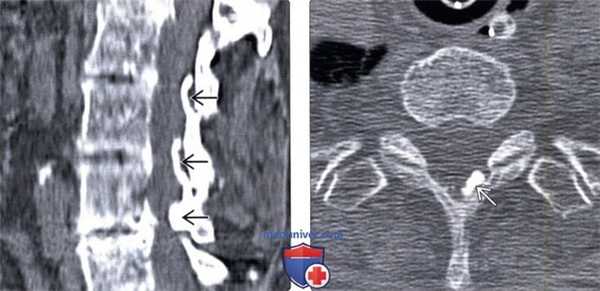

(Слева) КТ, сагиттальный срез: признаки оссификации желтых связок с умеренным стенозированием спинномозгового канала. Оссификация желтых связок грудного отдела позвоночника - это наиболее распространенная форма заболевания.

(Справа) КТ, аксиальный срез, пациент, исследование которому выполнено по поводу травмы: фокальная узелковая оссификация желтой связки, ставшая в данной ситуации случайной находкой.1. Общие характеристики: